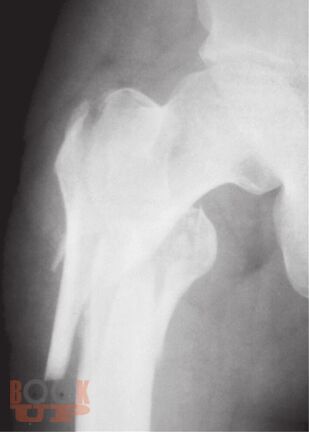

В настоящих методических рекомендациях обобщены научные данные и личный профессиональный опыт организации рентгеновской службы, описаны методы лучевой диагностики. Освещаются методы исследования органов и систем человека с нормальной анатомией, эмбриогенезом, рентгеноанатомией, а также рентгеносемиотика различных патологических состояний у взрослых и детей.